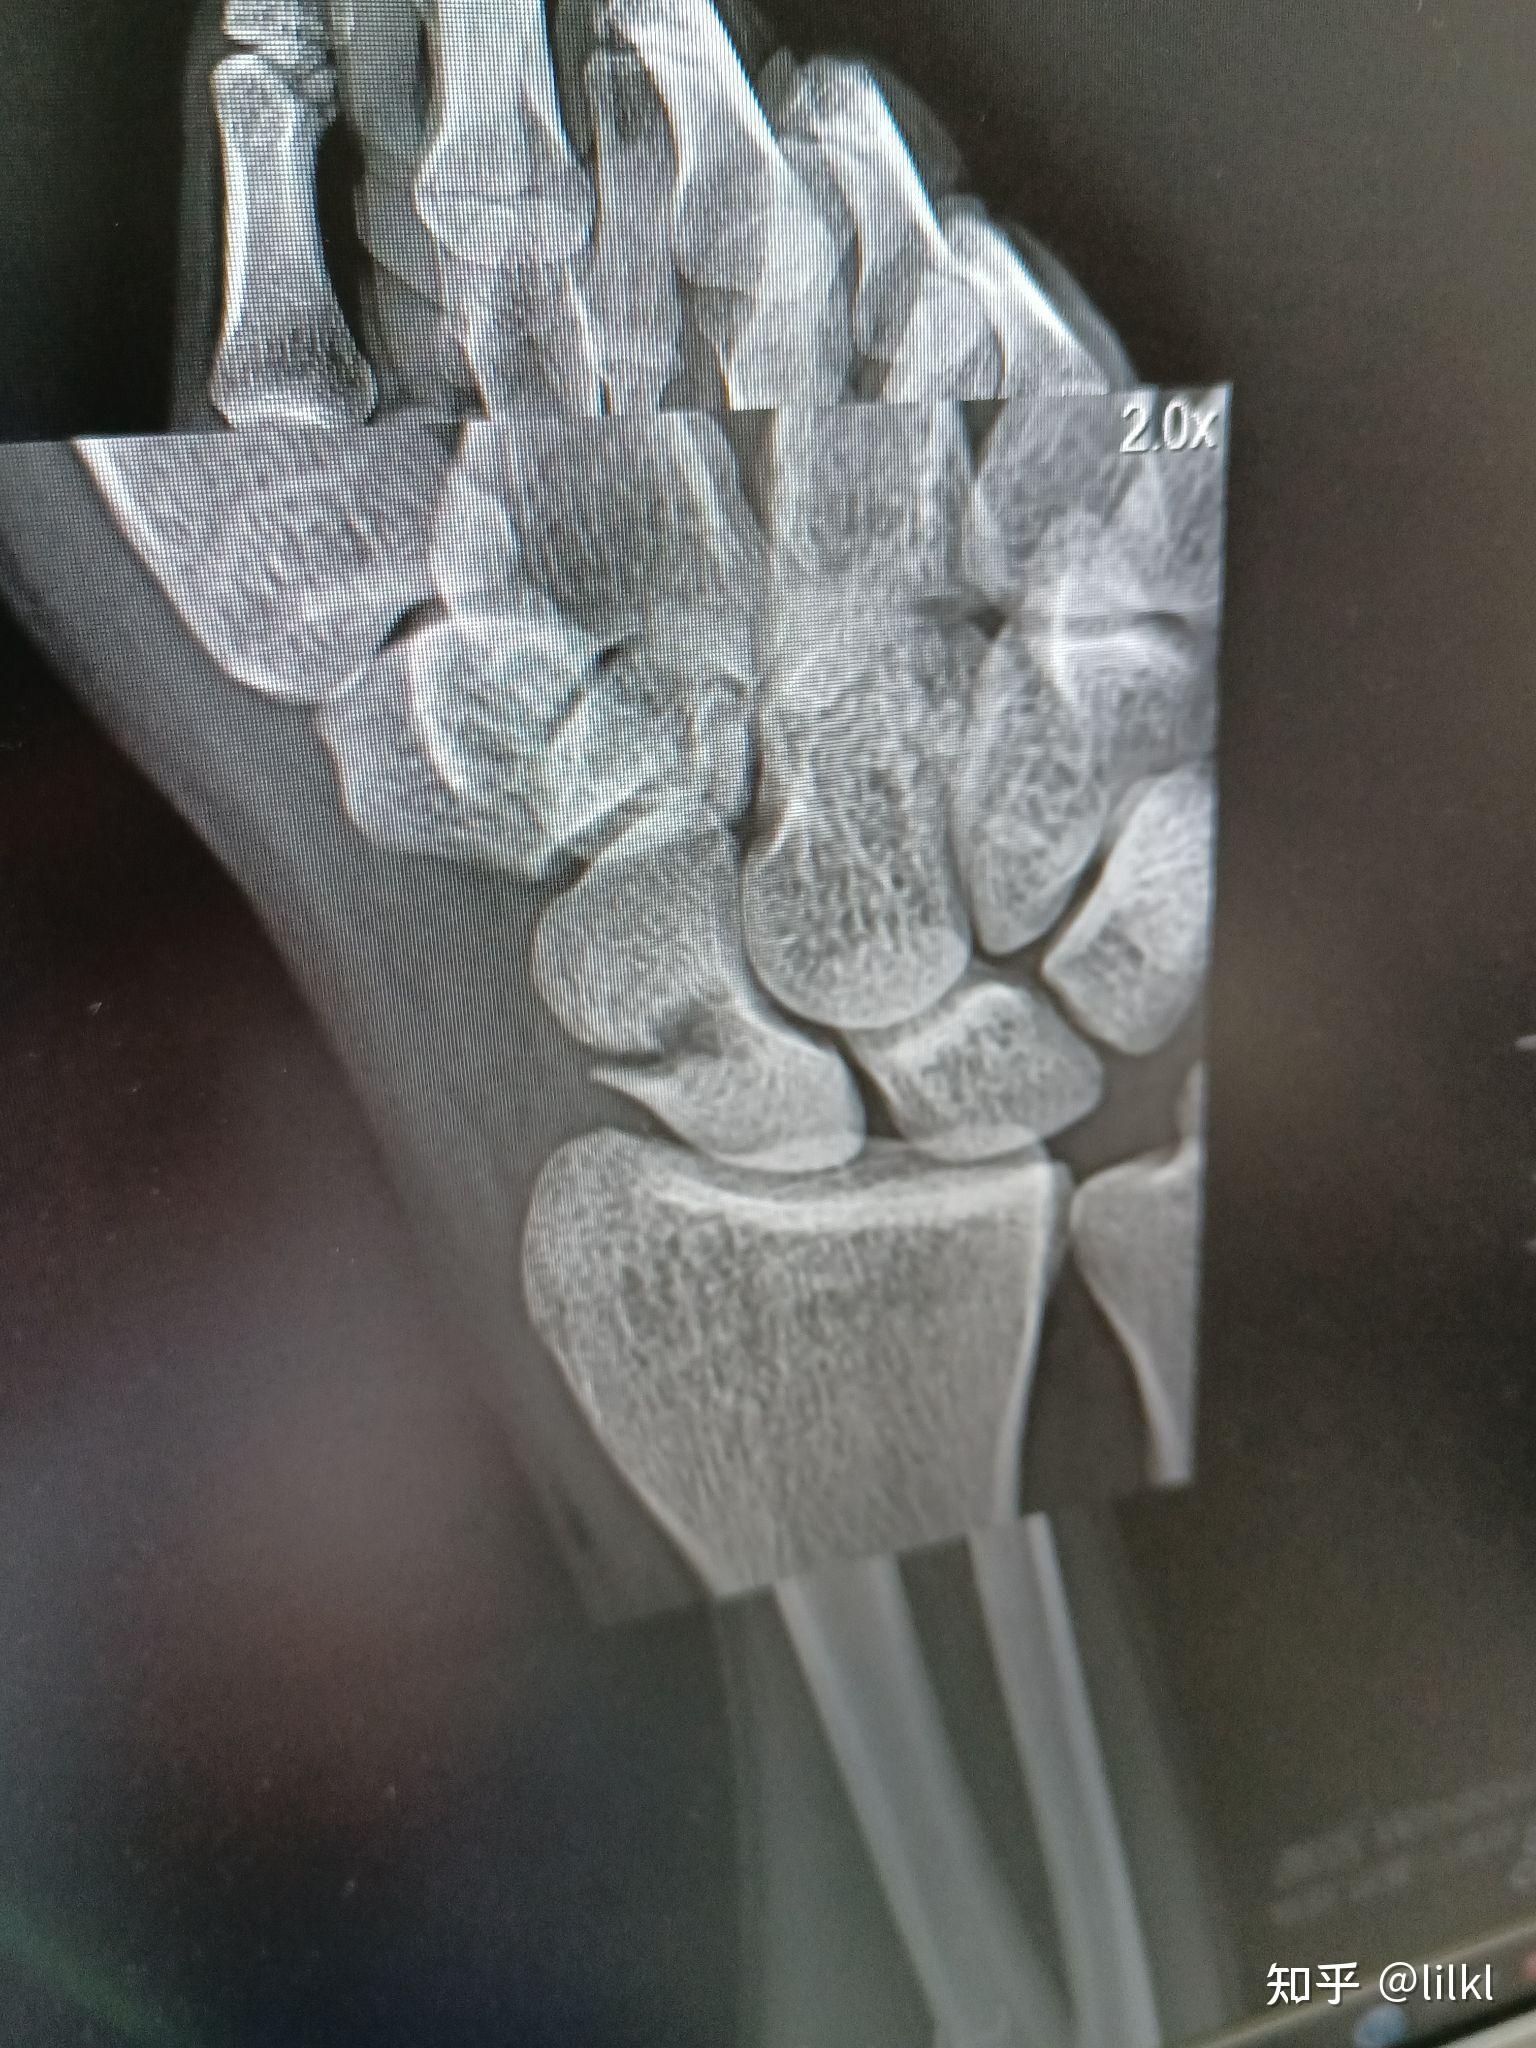

请教,经舟状骨月骨周围脱位一例,手术已做,请指正.

图片尺寸2592x1944